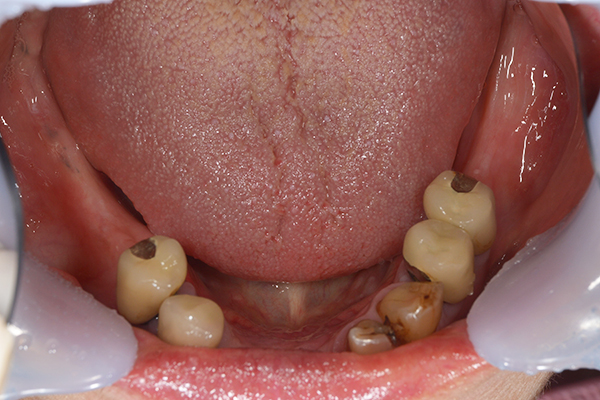

上下の入れ歯が外れやすくなったということでいらっしゃいました。 顎の骨はしっかりしていましたので、精密な型取りさえすればしっかりした入れ歯がつくれると思いました。 また下には6本歯が残っていましたが、虫歯になっている歯もありました。 かぶせ物のなかで大きな虫歯があった歯があり、1本だけ残せない状態でした。

上の入れ歯は確かに吸着は甘くなっていました。 また下の入れ歯はバネの一部が壊れており、安定感がなくなっていました。

精密な型取りの後、噛み合わせのチェックをしていきました。 かぶせ物も同時に作っていきました。